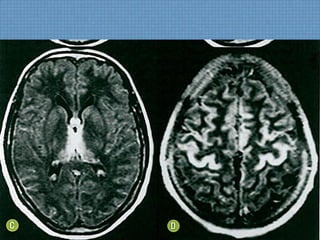

ACHADOS DE IMAGEM

– Atrofia cerebral e cerebelar;

– Perda da interface SB-SC;

– Hiperssinal T2/FLAIR simétrico em pedúnculos cerebelares

médio e braço posterior da cápsula interna;

– Afilamento do corpo caloso;

– Hiperssinal de SB também pode ser visto;

Hipossinal em T2 em núcleos denteados cerebelares,

tálamo, SN e núcleos rubros indica deposição de Fe;

INTOXICAÇÃO POR TOLUENO

INTOXICAÇÃO POR

TOLUENO